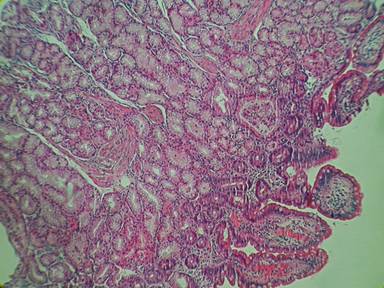

A 53-year-old man affected by multiple sclerosis referred to us for suspected intestinal sub-occlusion. Physical examination showed abdomen tense, with diffuse pain to deep palpation. Laboratory evaluation, abdominal ultrasound and X-ray were normal. A contrast-enhanced CT revealed a marked thickening of duodenal walls with enlargement of the head of the pancreas, with no certain cleavage plane with the duodenum. The pancreatic body presented a solid area of 4 cm of diameter. Upper gastrointestinal endoscopy was performed, revealing duodenal sub-stenosis, with mucosal hyperemia and edema (Figure 1). Biopsies established a diffuse Brunner’s gland hyperplasia without any sign of neoplasia (Figure 2). Therefore, EUS was performed and showed, at the sub-stenosis of the duodenum, a hypoechoic thickening wall with loss of normal stratification extending to muscularis and which seemed infiltrate the pancreatic parenchyma (Figure 3). Multiple lymph nodes near the pancreas were described. The body of the pancreas appeared diffusely heterogeneous and inside it and close the superior mesenteric artery, was observed a hypoechoic area of 4.3 cm of diameter with irregular margins, that showed a stiff consistency to the elastosonography (Figure 4). FNA of this lesion was performed and the cytological analysis showed signs of acute and chronic pancreatitis with no evidence of malignancy (Figure 5). The suspicion of malignancy was very high (according to radiological and endoscopic images), so we repeated upper gastrointestinal endoscopy with biopsies and EUS-FNA showing only a diffuse Brunner’s glands hyperplasia and cytological findings of pancreatitis. In view of clinical improvement, with gradual resolution of sub-occlusion and exclusion of malignancy we discharged the patient and decide to perform an endoscopic follow-up into three months. Three months after the patient was asymptomatic and on follow-up upper gastrointestinal endoscopy, duodenal sub-stenosis improved and histology confirmed Brunner hyperplasia.

Figure 2. A histological section from an endoscopic sample of duodenal mucosa demonstrating Brunner glands hyperplasia and normal villi (lower right). Hematoxylin and eosin, x200. |